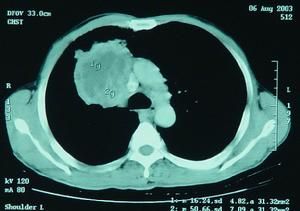

CT掃描及MRI檢查可出現病灶。